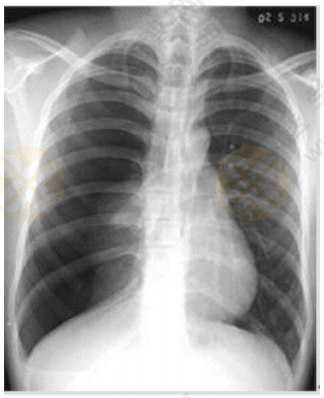

2022年中西医执业医师实践技能【西医临床答辩】02号题:根据下图所给X线片分析临床意义

根据下图所给X线片分析临床意义。(5分)